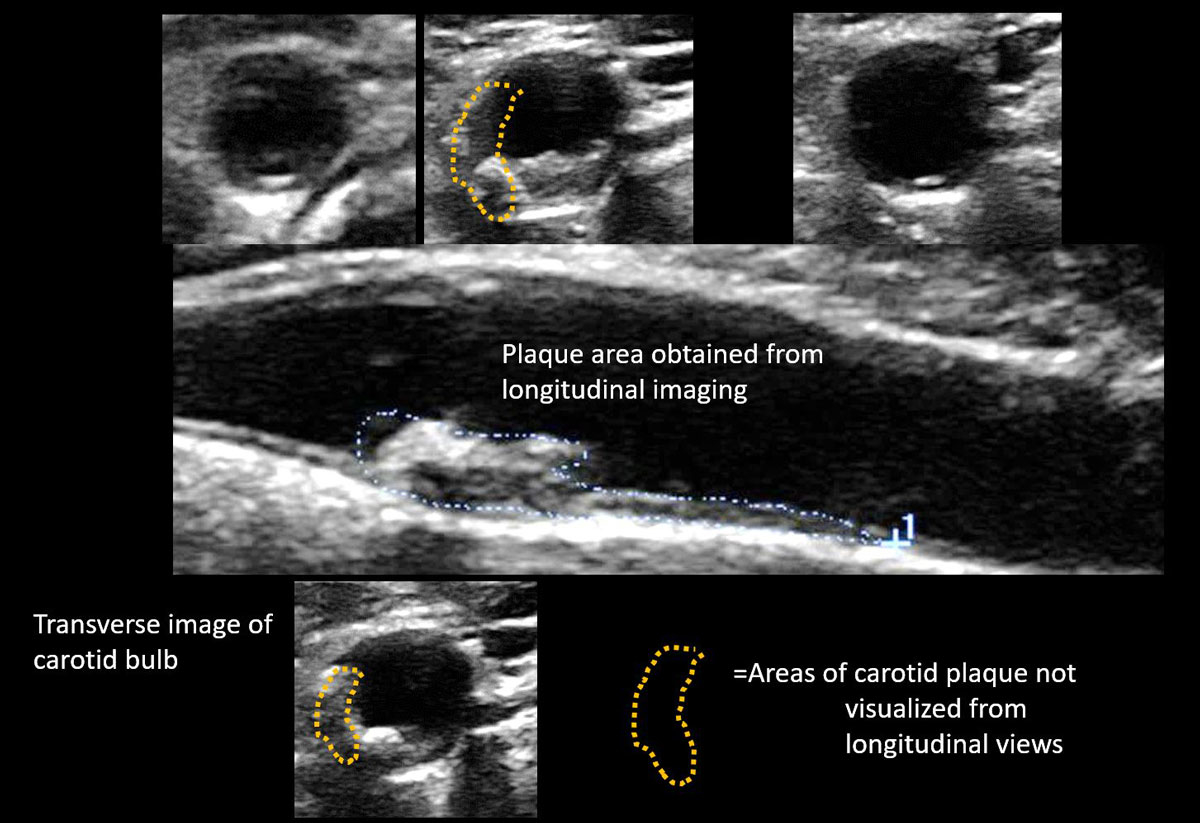

Given the excellent predictive accuracy for cardiovascular events of carotid TPV, which is indeed comparable to presence [65] and extent of coronary calcifications [34], it might be argued that carotid TPV should be used instead of carotid TPA. The correlation between carotid TPV and TPA was tested by the core laboratory in Ontario, Canada, which showed an extremely good correlation: r2 = 0.921 (p <0.0001) [19]. TPA has been shown to change by about 10 mm2 per year, which makes it suitable for observing therapeutic effects over time [20, 71]. In order to avoid the problem of missed plaques situated in the lateral wall with TPA, plaque area may be measured from transverse images (fig. 6).

Figure 6 Large carotid plaque in the carotid bulb, which contains plaque formation not visible in the longitudinal image.